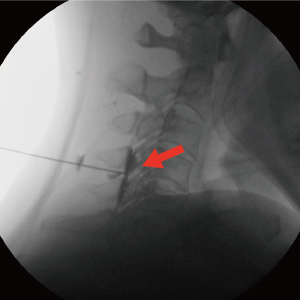

Treatment until the last painC-arm(특수영상치료장치)을 보며 치료하는 척추 비수술치료로 척추의 신경을 둘러싸고 있는 경막 바깥쪽에 약물을 투입하는 시술입니다. 허리 또는 목의 손상된 척추 부위에 가는 바늘을 통해 직접적으로 약물을 투입함으로써 신경 주위 염증과 부종을 가라 앉히며, 자율신경계의 정상적인 반응을 유도하는 치료입니다.

국소마취 하 디스크와 신경 사이에 정확히 바늘을 삽입하여 신경을 안정시키고 염증을 완화시킵니다.